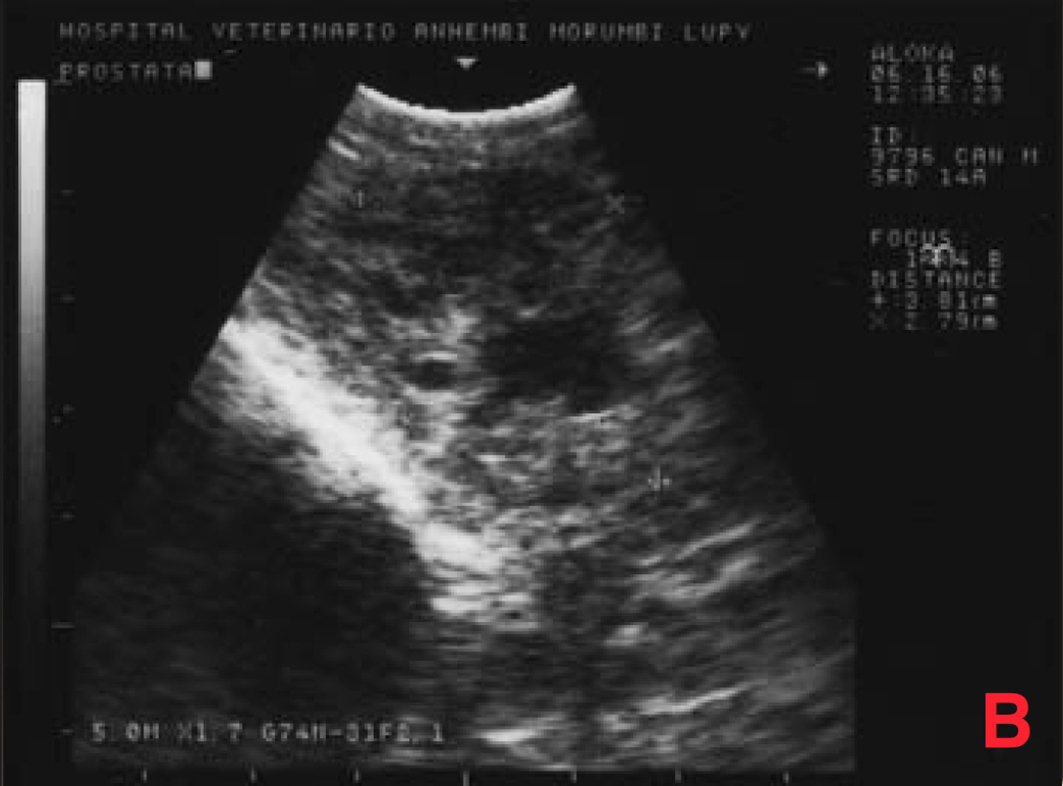

O exame ultrassonográfico demonstrou aumento de próstata mais acentuado (6 x 5 x 5,6 cm), com áreas císticas/cavitárias difusas pelo parênquima (sugestivas de hiperplasia prostática benigna/prostatite/neoplasia) e aumento de cadeia de linfonodos sublombares e ilíacos (5 x 4,6 x 4 cm), com ecogenicidade e ecotextura heterogêneas, sugestivo de processo metastático (Figura 9).